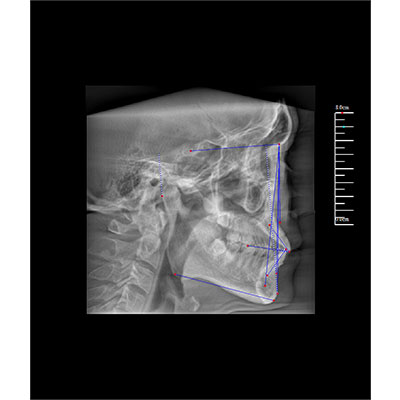

專有三維重建算法,可提供任意位置高清斷層影像。

可同時觀察軸向面、冠狀面和矢狀面圖像,方便臨床診斷。